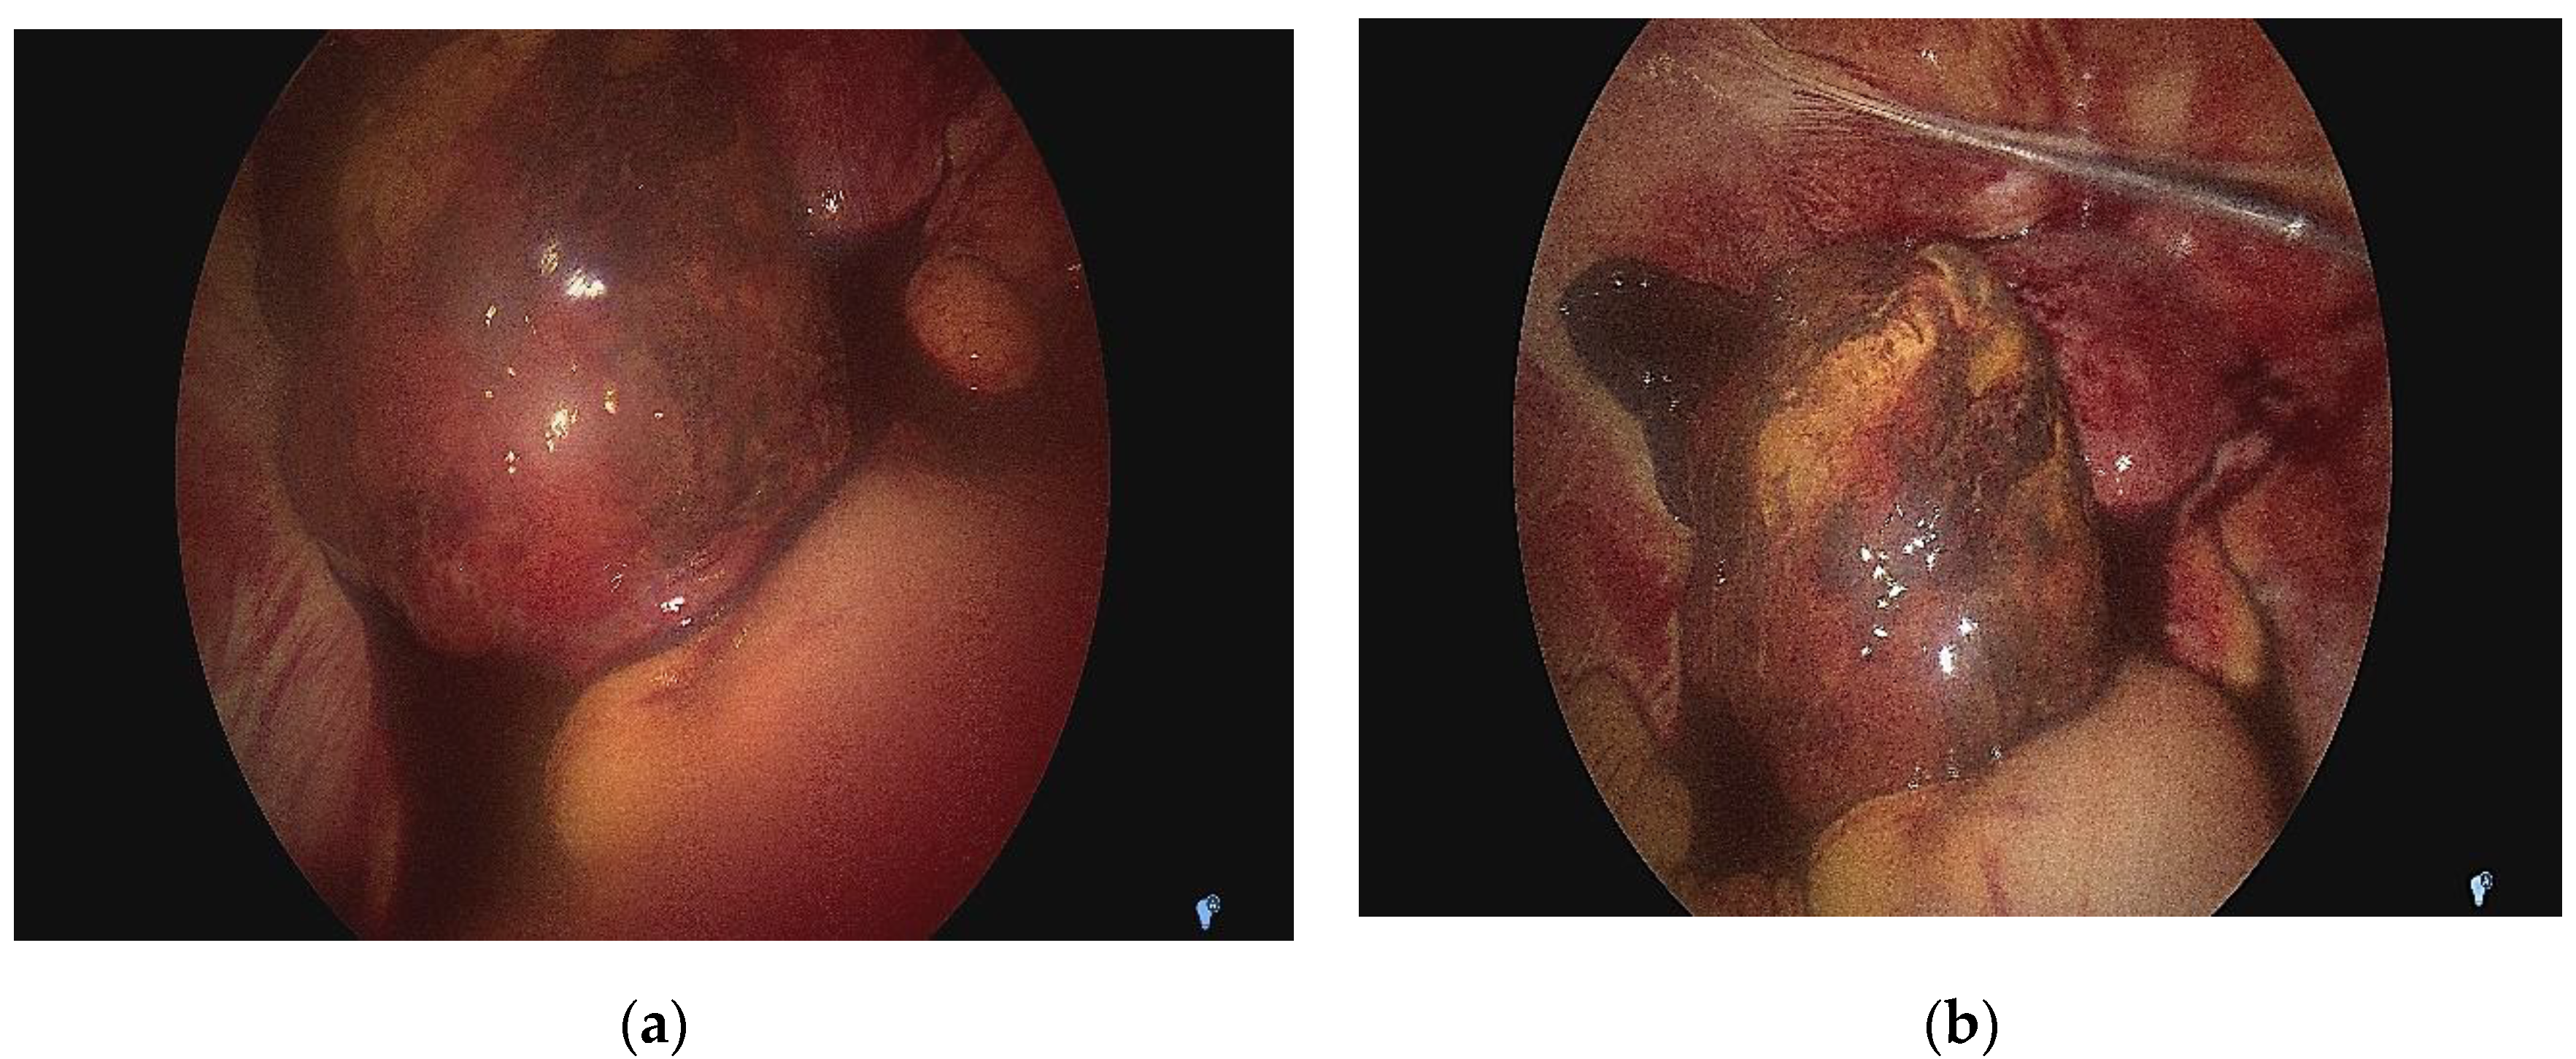

2. Case Presentation

2.2. Clinical History

2.3. Diagnostic Assessment and Investigations